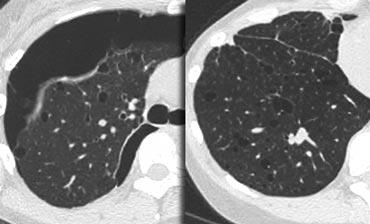

Hình bên trái là một trường hợp bệnh bụi phổi silic cho thấy các nốt có kích thước khác nhau với phân bố ngẫu nhiên và dưới màng phổi.

Một nốt có chứa vôi hóa (mũi tên).

Lưu ý sự vắng mặt của kiểu phân bố theo đường bạch huyết (quanh phế quản-mạch máu và dọc theo các khe liên thùy), vốn là gợi ý của bệnh sarcoidosis.

Cùng bệnh nhân bụi phổi silic như các hình trước, cho thấy một khối tập hợp ở vị trí cạnh rốn phổi thuộc thùy trên phổi phải. Thùy trái cho thấy nhiều nốt có kích thước khác nhau.

Chẩn đoán phân biệt bệnh bụi phổi silic / Bệnh bụi phổi.

- Sarcoidosis: có thể khó phân biệt (chú ý đến phân bố của các nốt).

- Nhiễm trùng: lao kê, nấm.

- Di căn theo đường máu: các nốt bụi phổi silic ở vị trí dưới màng phổi và quanh tiểu phế quản đến mức tiểu thùy phổi thứ cấp, có thể có phân bố có vẻ ngẫu nhiên và mô phỏng di căn cũng như nhiễm trùng dạng kê.

- Bệnh mô bào Langerhans: có thể khó phân biệt với bệnh bụi phổi silic ở giai đoạn sớm, khi LCH chỉ đặc trưng bởi sự hiện diện của các nốt nhỏ. Chú ý tìm các nốt có tạo hang.